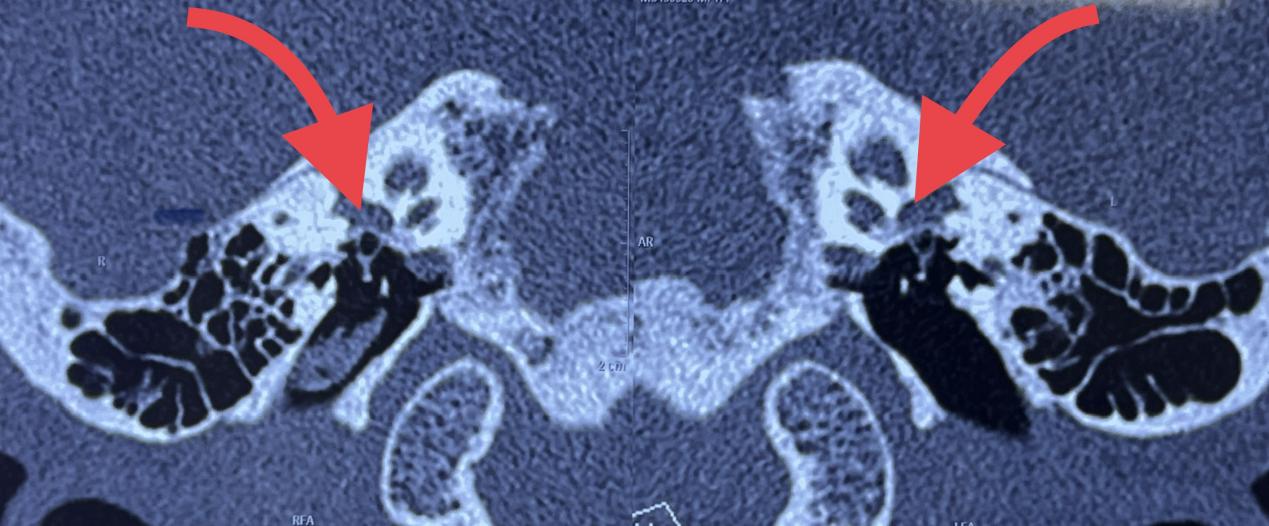

病例1:李某,男,47岁,主诉:双耳渐进听力下降3年,纯音听阈测定:双耳混合性聋,耳内镜:双耳鼓膜完整,听骨链三维重建示双耳耳硬化症(窗型)。

部分术前检查

病例2:郭某,女,35岁,主诉:双耳进行性听力下降半年,纯音听阈测定:双耳传导性聋,耳内镜:双耳鼓膜完整,听骨链CT三维重建示双耳耳硬化症。